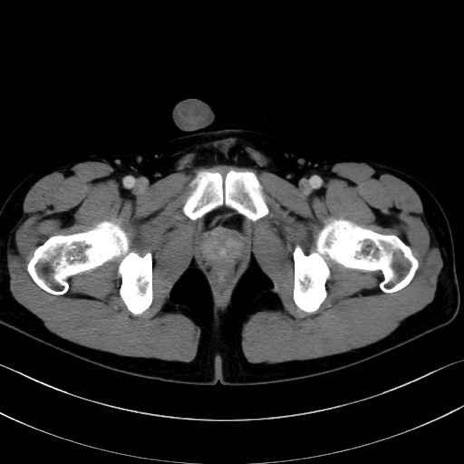

短内転筋(Adductor brevis) のCT画像の解剖

短内転筋 (Adductor brevis)